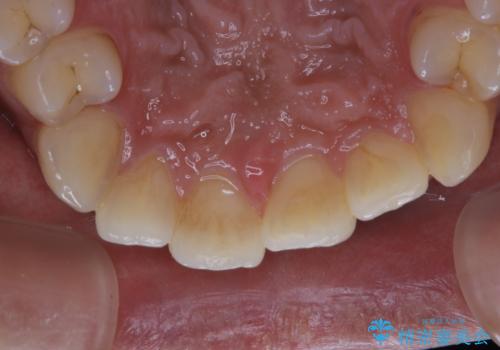

タバコによる着色をPMTCできれいな白い歯に

- タバコによる着色を綺麗にしたいとのことで来院されました。PMTC60分コースを行いました。

タバコに含まれているものの中で、タールというものが歯の黄ばみの原因です。その黄ばみなどを、無理に落とそうとしたりすると歯の表面に傷がついてしまったり余計に汚れがつきやすい状態になることがあります。

PMTCでは、歯の表面の凸凹にミネラルを補給して、ツルツルの表面に仕上げます。定期的にPMTCを行うことにより、歯質の強化になり着色がつきにくい状態になります。